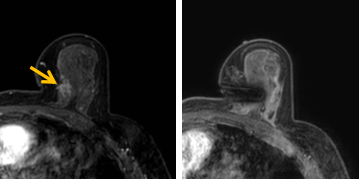

患者李女士磁共振檢查發(fā)現(xiàn)右乳內(nèi)側(cè)高度可疑病變,病變小摸不到,超聲和X線(xiàn)攝影(鉬靶)都看不到,怎么辦?要想明確病變性質(zhì),必須進(jìn)行磁共振引導(dǎo)下精準(zhǔn)足量的活檢,但是這種技術(shù)操作難度大、軟硬件要求高。

經(jīng)過(guò)仔細(xì)查體并分析所有影像資料,陳寶瑩發(fā)現(xiàn),病變靠近胸大肌,容易造成術(shù)中損傷?;颊呷榉枯^小,病變?cè)趦?nèi)側(cè),導(dǎo)致乳房不易固定,進(jìn)針難度大,與患者充分溝通后,陳寶瑩帶領(lǐng)團(tuán)隊(duì),制定了細(xì)致的操作方案,術(shù)中,醫(yī)護(hù)團(tuán)隊(duì)反復(fù)調(diào)整體位和固定架的角度及方向,利用隔離技術(shù)保護(hù)好周?chē)M織。受乳房形態(tài)和病變位置的限制,醫(yī)生只能蹲著、跪著進(jìn)行操作,經(jīng)過(guò)30多分鐘終于順利完成,精準(zhǔn)獲取了足量的組織,而且一針到位,創(chuàng)傷小、出血少,患者沒(méi)有任何不適,做完即回家休息。幾天后,病理證實(shí)是一種特殊類(lèi)型的早期乳腺癌,為后續(xù)進(jìn)一步治療方案的制訂提供了準(zhǔn)確依據(jù)。